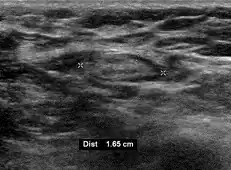

Medical ultrasonography of a typical normal lymph node: smooth, gently lobulated oval with a hypoechoic cortex measuring less than 3 mm in thickness with a central echogenic hilum.[26]

Ultrasonography of a suspected malignant lymph node:

- Absence of the fatty hilum

- Increased focal cortical thickness greater than 3 cm

- Doppler ultrasonography that shows hyperaemic blood flow in the hilum and central cortex and/or abnormal (non-hilar cortical) blood flow.[26]

On ultrasound, B-mode imaging depicts lymph node morphology, whilst power Doppler can assess the vascular pattern.[28] B-mode imaging features that can distinguish metastasis and lymphoma include size, shape, calcification, loss of hilar architecture, as well as intranodal necrosis.[28] Soft tissue edema and nodal matting on B-mode imaging suggests tuberculous cervical lymphadenitis or previous radiation therapy.[28] Serial monitoring of nodal size and vascularity are useful in assessing treatment response.[28]